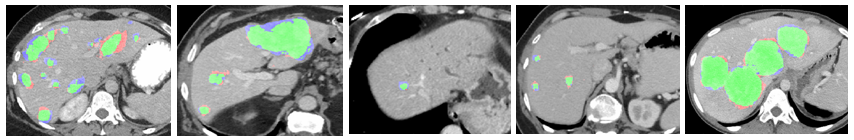

Figure 1: (a) Liver patch examples: lesion (blue), normal-interior (red) and normal- boundary (yellow); (b) Patch size 20×20202020\times 20 [I] and patch size 50×50505050\times 50 [II]. Top row: lesion boundary patch examples; Bottom row: liver boundary patch examples.

2 Multi-class patch-based CNN system

We propose a system for lesion detection, which is based on localized patch classification into lesion vs non-lesion categories. Patches are an important representation to address the data limitation challenge, critical for modeling small and rare events such as lesions. Fig. 1a shows examples of lesion patches, including lesion-boundary patches (shown blue zoomed-in), as well as patches from the non-lesion category, which include both normal-interior patches (red) and normal-boundary patches (yellow). As can be seen in Fig. 1b[I], liver boundary and lesion boundary areas may look alike and are difficult to distinguish when using small patches. When using a larger size window, a clearer distinction between the two categories is possible, as seen in Fig. 1b[II]. This motivated us to use two different scales (patch-sizes) within the proposed system to capture both the local fine details and the more global spatial information.

Figure 3: Examples of lesion detection results. First row: Parallel multi-class CNN. Second row: Binary-class CNN. TP marked in green, FP in red and FN in blue.

Detection results can be seen in Fig. 3. The information retained from the sub-categories improves the detection performance and the robustness of the system as compared to the binary-class implementation. It reduces the false-positives in the normal tissue mainly at the liver boundary but also in the interior area of the liver.

Figure 4: Examples of lesion detection results showing the variability in lesions size, location and shape. TP marked in green, FP in red and FN in blue.